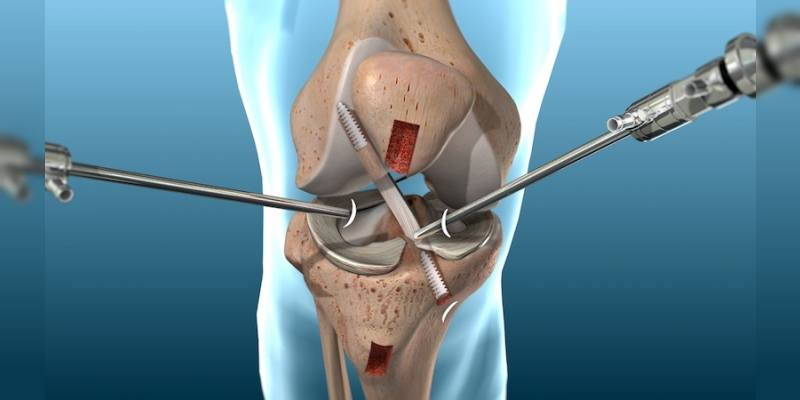

Dr. Ankur Singh is a highly experienced Senior Orthopedic Surgeon with over 15 years of expertise in Arthroscopy, Sports Medicine, Arthroplasty and Robotic Joint Replacement. He specializes in advanced knee, shoulder and hip surgeries, including primary, complex, and revision joint replacements, ligament reconstructions, cartilage restoration, osteotomy and joint preservation procedures.

Advanced 3D surgical mapping and robotic systems allow millimeter-level accuracy and optimized implant positioning.